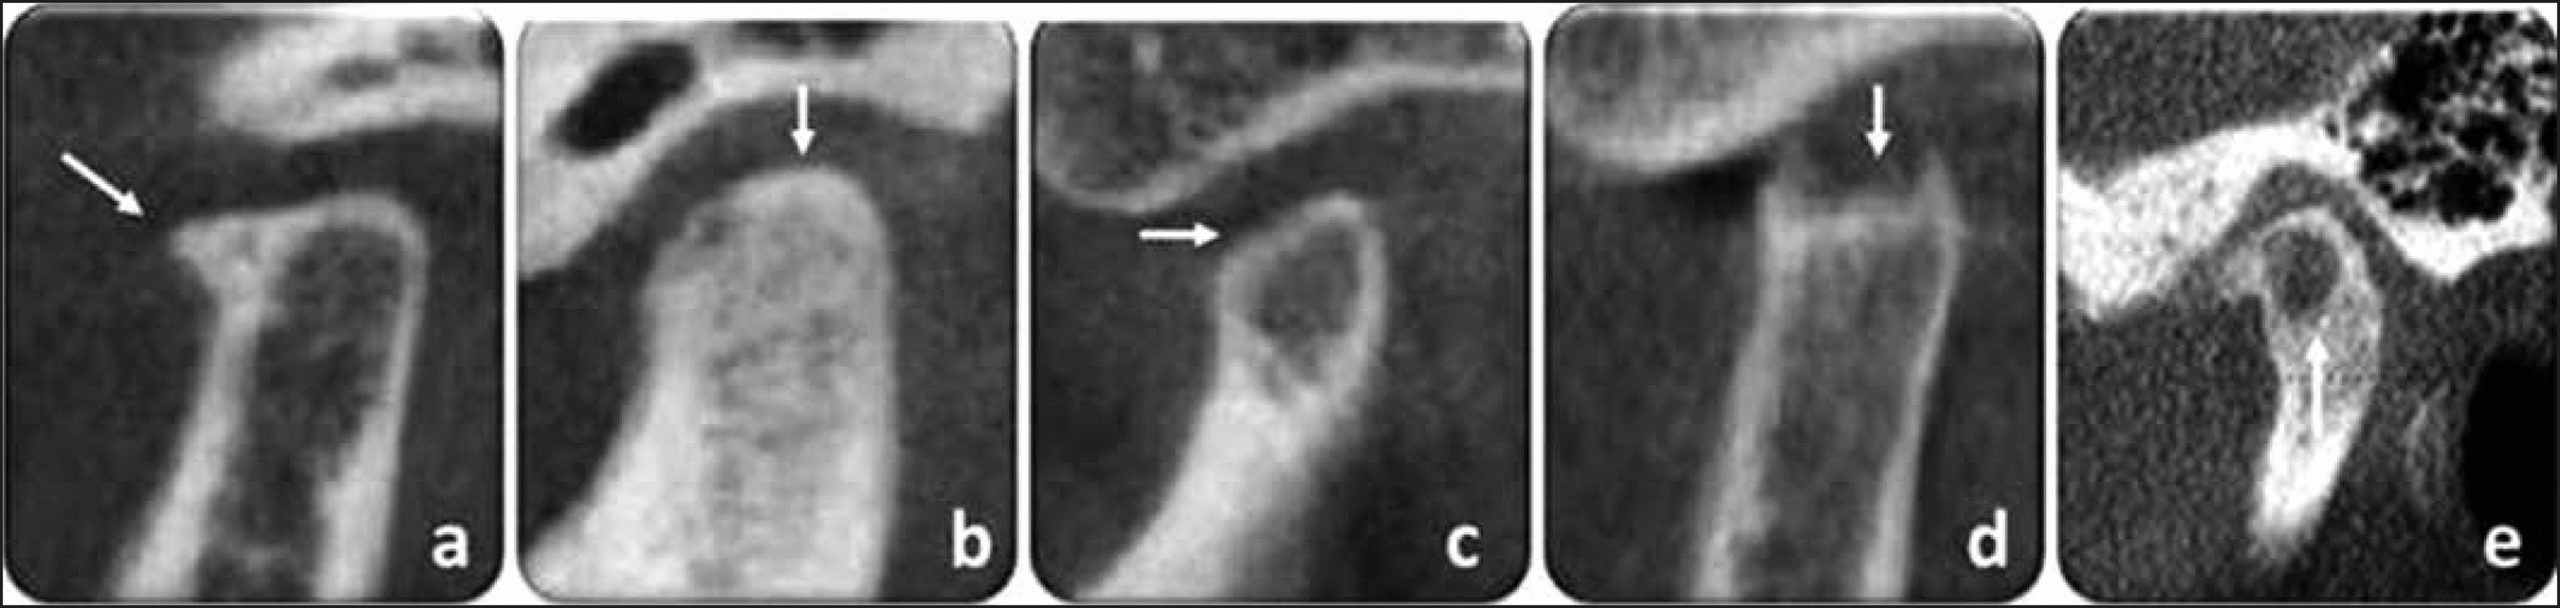

Imagem de tomografia computadorizada de feixe cônico de diferentes articulações temporomandibulares com comprometimento anatômico, indicando degeneração articular, analisadas em cortes parassagitais (a) presença de osteófito (como se fosse um “bico de ave”) na região da cabeça mandíbular; (b) esclerose; (c) aplainamento; (d) erosão; (e) esclerose generalizada na região do tubérculo articular e pseudocisto subcondral na cabeça da mandíbula.

Fonte: https://doi.org/10.5935/2595-0118.20200045